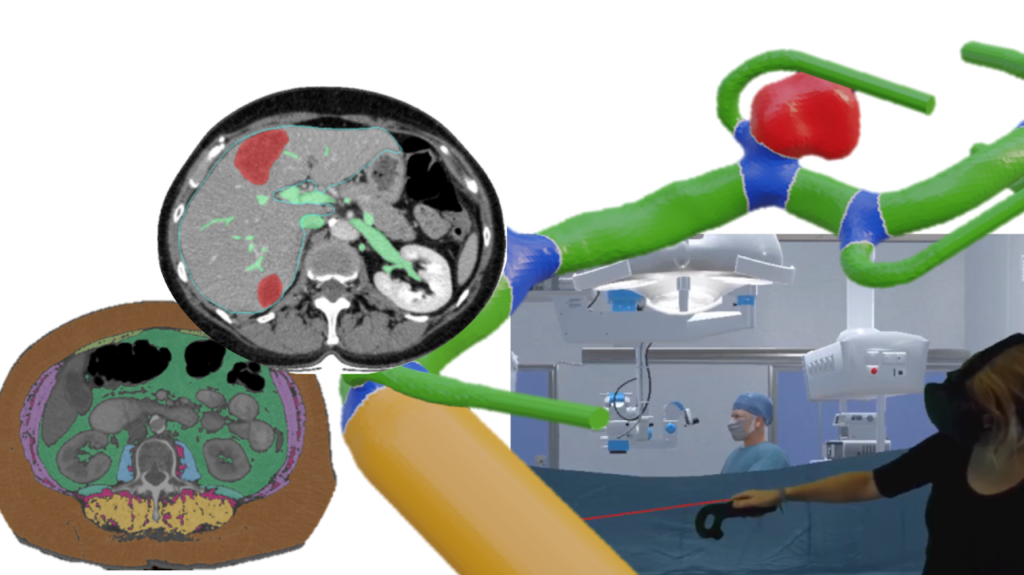

Master Thesis – Geometric Deep Learning for Liver Resection

This project focuses on pre-operative liver resection risk analysis using geometric data (meshes, point clouds). Such representations support advanced AR/VR tools and provide a realistic, intuitive understanding of surgical resection planning.

(Manual) Vessel Segmentation

We are looking for a student assistant („Hiwi„) for carrying out vessel segmentation in tomographic image data. After the segmentation, a transformation into 3D surface models should be carried out, including postprocessing of the surface meshes.

Vessel Tree Analysis

We want to develop an automatical vessel tree analysis tool for medical vascular structures. This is important for tumor surgery planning (which vessel should be spared? which vessel is at risk by the tumor location? …) but also for stroke analysis (which vessel supporting the brain might be hampered?).

Virtual Reality for Surgery Planning

We are looking for a student interested in developing virtual reality (VR) applications using Unity for support of liver surgery planning. The VR project should include gamification aspects (like high scores etc.) to engage the medical users and increase their motivation.